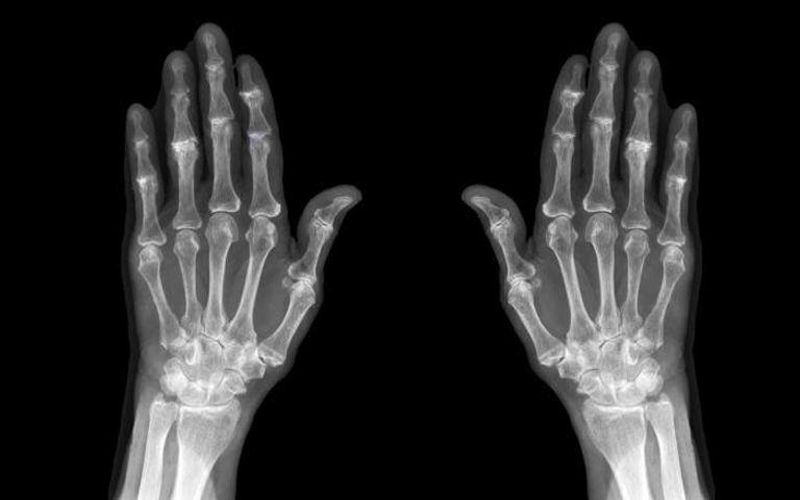

نيسان ـ يعاني عدد كبير من الأشخاص من هشاشة العظام وتزداد نسب الإصابة به بين من هم أكبر سنا والنساء وهو من أكثر الأمراض الصامتة التى لا تظهر أعراضا واضحة إلا بعد التمكن من جسد المريض.